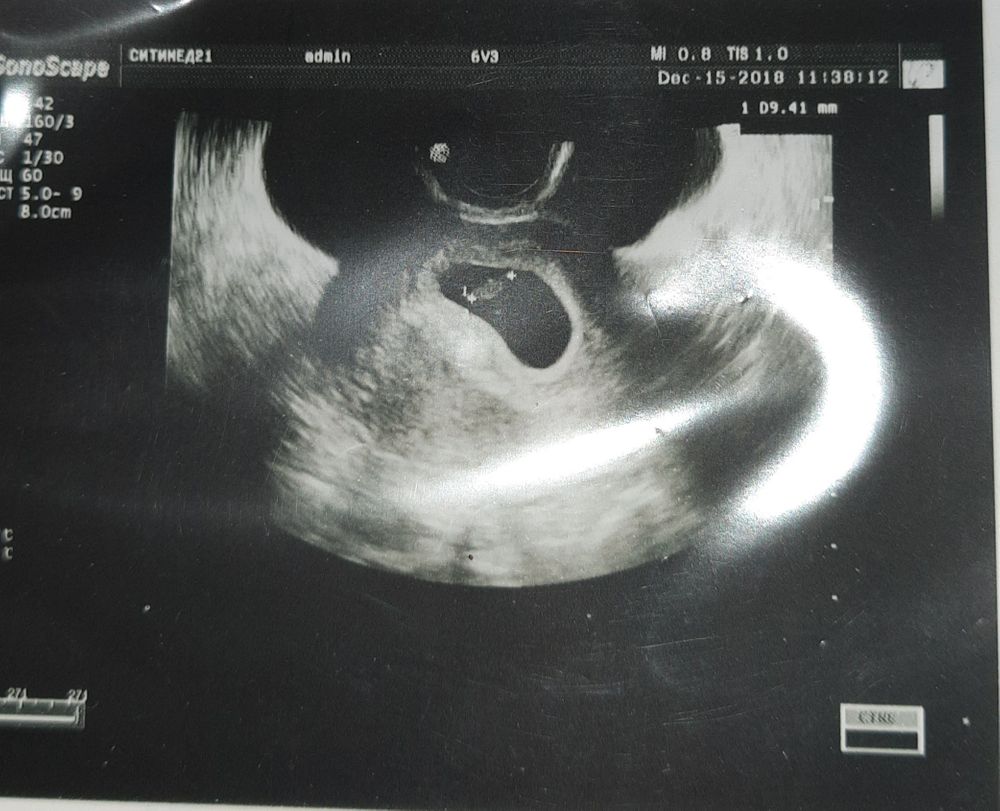

Пол малышаДевочки, всем привет. Увидела этот метод определения пола. Стало очень интересно. Посмотрите, как думаете, кто будет? УЗИ на 7 неделе было трансвагинально.

Наталья, тут девочка да. Смотрят не положение эмбриона, а хориона, это белый ободок вокруг плодного яйца